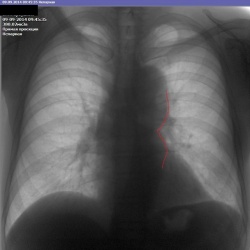

Пришел пациент лечиться с правосторонней пневмонией, а на контроле оказалось, что пневмония левосторонняя. И все слышали хрипы справа в области лопатки Первый снимок не маркирован, вот про...